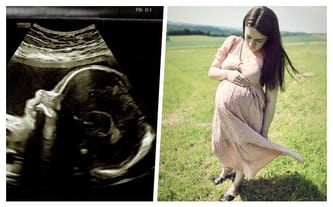

Radość oczekiwania przerwana brutalną diagnozą. Łucja w brzuchu mamy jest bezpieczna, ale tuż po przyjściu na świat rozpocznie dramatyczną batalię. Musimy zrobić wszystko, by pierwszy oddech naszej córeczki nie był ostatnim. Pomocy!

Trzecia ciąża, trzecia pociecha, pełne emocji oczekiwanie całej rodziny. Kolejna standardowa wizyta u lekarza, która na zawsze zostanie w naszej pamięci. Początkowo usłyszeliśmy o podejrzeniu nieprawidłowości, ale to uruchomiło całą machinę: strachu, kolejnych konsultacji, rozpaczliwego poszukiwania ratunku. Nadziei, która nie opuściła nas do dzisiaj.

Diagnoza - krytyczna wada serca - stenoza aorty z restrykcyjnym otworem owalnym odwróciła nasze życie do góry nogami.

Kiedy lekarze w Polsce przekazali informację o możliwości leczenia Łucji w Austrii, nie mogliśmy czekać. Właściwie rzuciliśmy wszystko i ruszyliśmy w drogę w pogoni za nadzieją na ratunek. Konsultacje z austriackimi specjalistami już za nami – zostaliśmy zakwalifikowani do operacji - pierwszy zabieg zostanie przeprowadzony jeszcze w życiu płodowym. Niestety, lekarze nie mogą czekać - termin może zostać wyznaczony za kilka dni! Niestety, to tylko pierwszy krok na drodze w walce o życie i zdrowie Łucji.